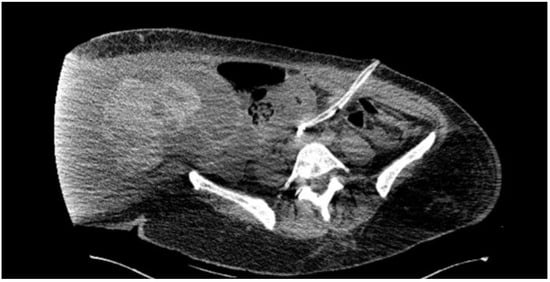

After the abdominal volume had decreased, the patient was transported to the CT scanner, which revealed the following findings: in the right abdominal flank, a space-occupying lesion was observed. This encapsulated lesion had irregular, well-defined contours, mixed fluid-hemorrhagic densities, and measured approximately 14.6 × 22 × 30 cm (Figure 2). Moderate free peritoneal fluid was present in the abdominopelvic cavity and hepato-splenomegaly was observed. The uterus was anteverted but could not be fully evaluated due to artifacts, appearing without suspicious lesions on the CT. Multiple mesenteric lymph nodes with short axis dimensions of up to 10 mm were noted, associated with mesenteric fat infiltration. Bilateral pleural effusions were present, with a maximum anteroposterior dimension of 14 mm. Additionally, there was an alveolar consolidation in the posterior basal segment of the right lung.

Figure 2. Computer tomography image in axial section plane at the level of the lower abdomen and pelvis revealing a cystic-type tumor.